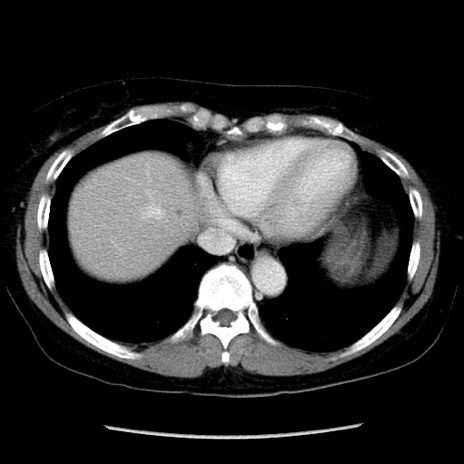

症例6(横断像)

【症例】50歳代女性

【主訴】下腹部痛

【現病歴】本日朝より下痢2回あり。 昼食を食べた後、嘔吐3回、下腹部痛認め、症状軽快せず、当院救急搬送。

最終食事:本日昼(生ものなし)。 昨日の夜、刺身を食ぺたとのこと。周囲に同様の症状の者なし。普段、排便は毎日あるとのこと。

【既往歴】卵巣癌術後(8年前に当院で卵巣摘出)

【身体所見】 意識清明、腹部:平坦、腸蠕動音→、やや硬、下腹部自発痛・圧痛あり、反跳痛あり、筋性防御なし。

【データ】WBC 16000、CRP 0.01